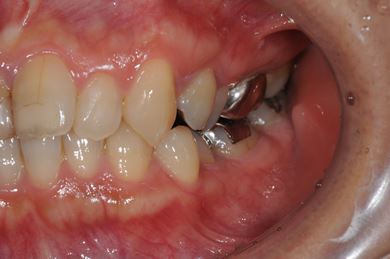

| 性別/年齢 | 女性 / 45歳 | ||||||||||||||||||||||||||||||||

| 主訴 | 右下奥虫歯による冠はずれと、前歯他冠治療済の他の虫歯の有無の確認。 | ||||||||||||||||||||||||||||||||

| 治療方針 | セラミック治療にて、審美的回復を行う。 | ||||||||||||||||||||||||||||||||

| 治療内容 | CAD/CAMオールセラミッククラウン3本(オールセラミック用土台3本)、ハイブリッドセラミックインレー2本 | ||||||||||||||||||||||||||||||||